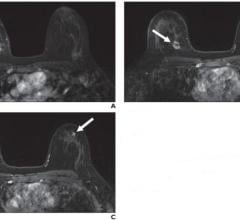

May 19, 2022 — According to ARRS’ American Journal of Roentgenology (AJR), axillary lymphadenopathy detected by breast ...

Despite decades of progress in breast imaging, one challenge continues to test even the most skilled radiologists ...